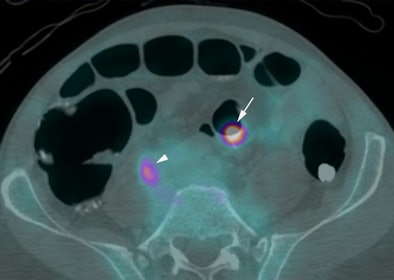

| Above, supine virtual colonoscopy image shows a 20-mm adenoma (arrow) in the sigmoid colon. Below, fused PET/CT in the same patient shows an area of intense F-18 FDG uptake corresponding to the 20-mm adenoma. A small amount of misregistration is present. Arrowhead points to ureteric activity. All images courtesy of Dr. Stuart Taylor. |

Of the 14 polyps that were 6 mm or larger in diameter, 12 (86%, 95% CI: 67%-100%) were avid for F-18 FDG, including all of the lesions 10 mm or larger (mean standardized uptake value [SUV], 10.1), Taylor and his team wrote. Moreover, the group found no significant difference in mean SUV for adenomas with (mean, 12.7) and without (mean, 7.4) high-grade dysplasia (p = 0.10).

A single 6-mm polyp missed on CTC was not F-18 FDG-avid, nor was there uptake in any polyp 5 mm or smaller.

CTC's sensitivity for polyps 6 mm or larger of 92.9% (95% CI: 79.4%-100%) did not improve with the addition of PET. However, the combined exam did improve the per-patient positive predictive value for a polyp 10 mm or larger from 73% (95% CI: 39%-92%)to 100% (95% CI: 60%-100%).